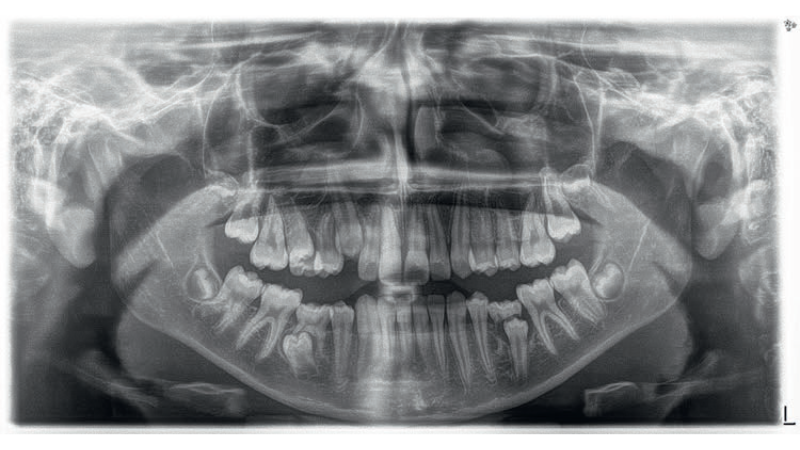

- Opisano przypadek pacjentki w wieku nastoletnim, z zatrzymanym zębem 45, mezjoinklinacją zęba 46 (jedna z cech objawu Godona) i zgryzem otwartym.

Streszczenie: Celem leczenia zgryzów otwartych jest poprawa wymiaru pionowego oraz uzyskanie właściwych kontaktów okluzyjnych, warunkujących prawidłową funkcję w obrębie narządu żucia. Praca przedstawia przypadek nastoletniej pacjentki, u której stwierdzono zgryz otwarty, posteriorotację żuchwy i wydłużenie dolnego piętra twarzy. Zaplanowano intruzję wspomaganą mikroimplantami. Takie zastosowanie zakotwienia szkieletowego stanowi alternatywę dla leczenia ekstrakcyjnego lub ortognatycznego (1). Leczenie pacjentki składało się z trzech etapów. Pierwszym z nich było szeregowanie i niwelacja zębów w celu uzyskania możliwości zastosowania pełnowymiarowych łuków stalowych, by podczas intruzji ograniczyć wychylenie zębów do policzka. W drugim etapie wykorzystano zakotwienie szkieletowe wspomagane blokami zgryzowymi. Trzecia faza leczenia polegała na wyrównaniu i wypoziomowaniu płaszczyzny zwarcia. Uzyskano pozytywny wynik leczenia zgodny z założeniami.